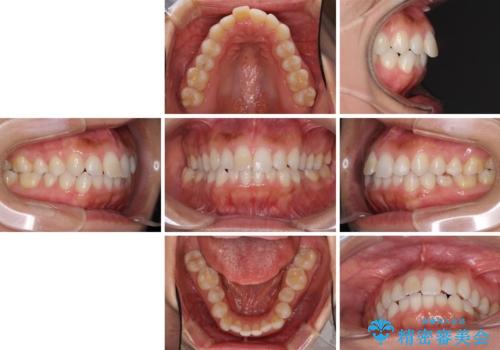

- 上下の前歯のデコボコと奥歯の反対咬合を気にして来院された患者様です。

インビザラインを用い、上下顎ともにIPR(歯と歯の間を削る)により叢生を改善することとしました。

奥歯の反対咬合は、骨格に由来するものであるため、改善できるところまで改善していくこととしました。

治療を長期化させたくないとのご要望があったので、左下の90度捻転した歯は、捻転した状態のゴールとしました。

反対咬合を改善したことで、歯ぎしりしたときの引っかかる感じがなくなり、奥歯への負担を大きく軽減することができました。